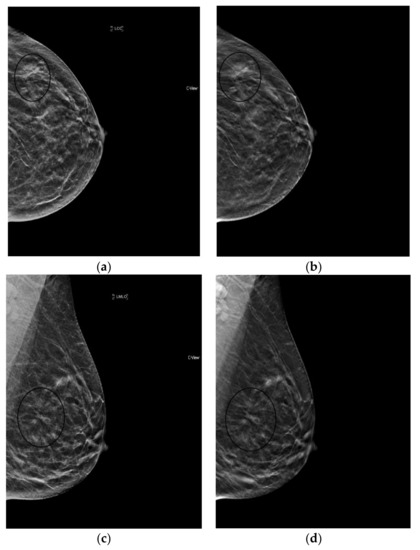

6.2. Calcifications

The processing algorithm to generate an s2D image enhances objects above a certain density threshold on s2D. In a phantom study, s2D provided better visualization of medium and large calcifications however smaller calcifications, especially fine calcifications with contrast similar appearance to background noise were harder to see [22]. On the contrary, in clinical use, a prospective review of 1206 screening exams found synthesized mammography to have significantly better conspicuity for calcifications compared to 2D FFDM (p < 0.001) [39].

This enhancement can also lead to parenchymal densities or ligaments falsely appearing as calcifications. Indeed, pseudo-calcifications are a recognized synthesized mammography artifact. When questioning the verity of a calcification finding, it is helpful to confirm identification in both planes, as well as on tomosynthesis images. Pseudo-calcifications will not be identifiable on both planes and may align with ligaments or vessels on tomosynthesis. Indeed, although reduced recalls for calcifications were seen with s2D+DBT compared to 2D FFDM, Freer et al. found calcification recalls were increased relative to 2D+DBT, which may reflect the effect of the pseudo-calcification artifact [31]. In contrast, Zuckerman et al. showed recall rates were lower for calcified lesions on s2D+DBT compared to 2D+DBT [28].

s2D+DBT was inferior to 2D+DBT and 2D FFDM alone for detection of microcalcifications and DCIS in the 11-20mm range in the TOMMY trial [32]. And specificity for calcifications has been shown to be lower compared to masses and asymmetries for both s2D and 2D FFDM [33]. Despite this, in situ cancer detection was not affected by decreased recall rates for calcifications in Freer’s study [31]. Furthermore, Choi et al. showed similar performance of s2D and FFDM in detection of calcified and non-calcified stage T1 cancers [34]. How synthesized mammography definitively affects the rate of cancers detected as calcifications remains to be fully validated. (Figure 2).

Figure 2.

Linear, heterogeneous calcifications (circled in black) best seen on synthesized mammography images (grade 2 ductal carcinoma in situ). (a) 2D FFDM (b) s2D (c) s2D zoom.